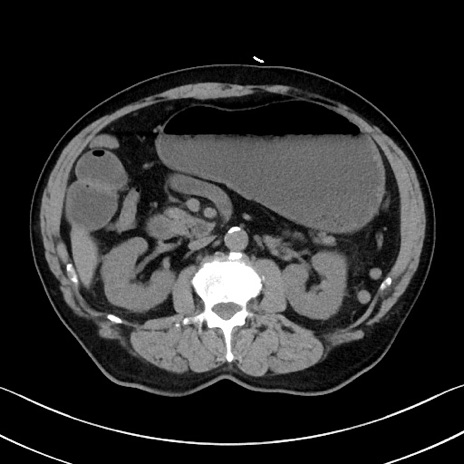

冠状断像

症例35(横断像)

【症例】70歳代 男性

【主訴】腹部膨満、嘔吐

【現病歴】昨日より腹部膨満感出現。本日増悪し、仙痛出現。嘔吐あり、受診。

【既往歴】糖尿病、胆摘後

【身体所見】BP 149/80mmHg、HR 74/min、BT 35.9℃、腹部:膨満、軟、圧痛なし。腸雑音減弱あり。上腹部正中切開瘢痕あり。

【データ】WBC 13500、CRP 1.72